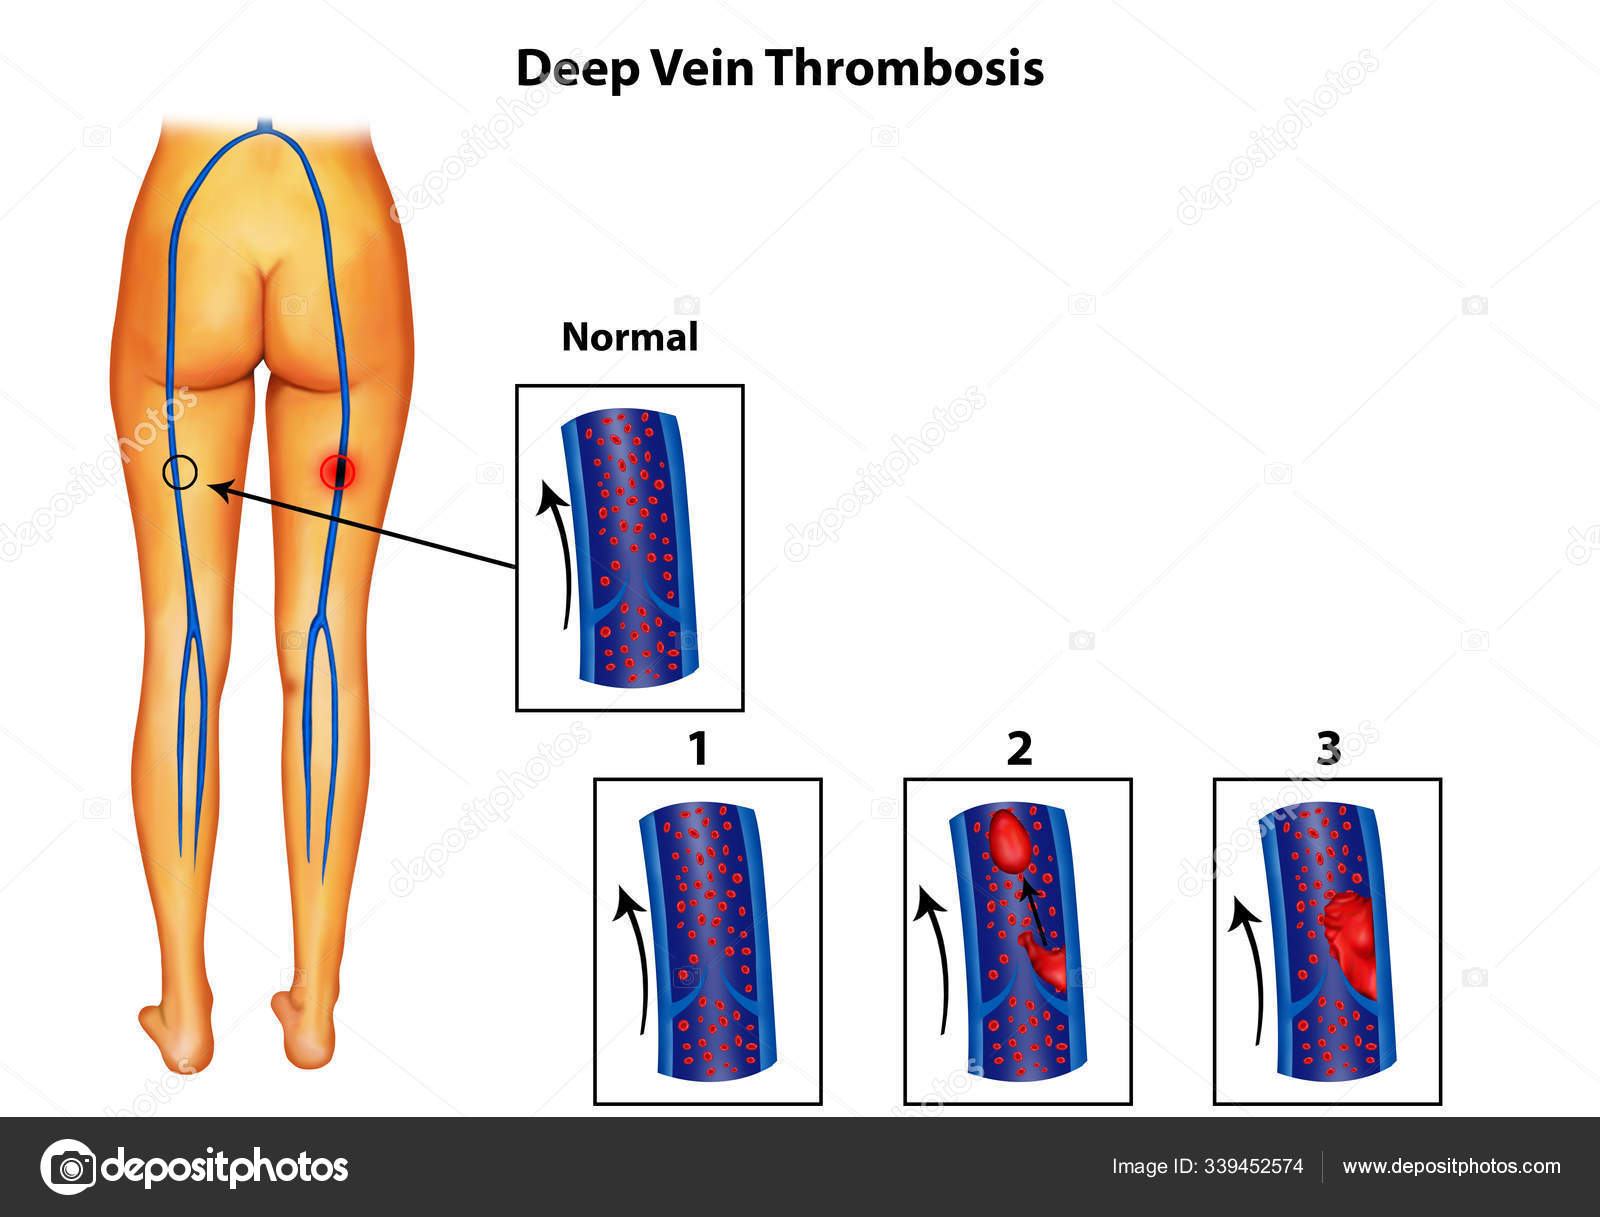

上皇后さまが発症された深部静脈血栓症について解説します下肢静脈瘤の原因・症状・治療方法・予防方法などを専門医が解説。

脚領域における深部静脈血栓症の医学的図。のイラスト素材・ベクター Image 98030310。

深部静脈血栓症 DVT の病態と予防見て!わかる!病態生理と看護 花子のまとめノート。

深部静脈血栓症 - 血栓のベクターアート素材や画像を多数ご用意 - 血栓, 肺塞栓症, イラストレーション - iStock。

深部静脈血栓症、血栓症。塞栓。正常静脈と静脈瘤の構造。イラストは私が作成しました写真素材1443942500Shutterstock。

深部静脈血栓症イラスト無料イラスト・フリー素材なら「イラストAC」。